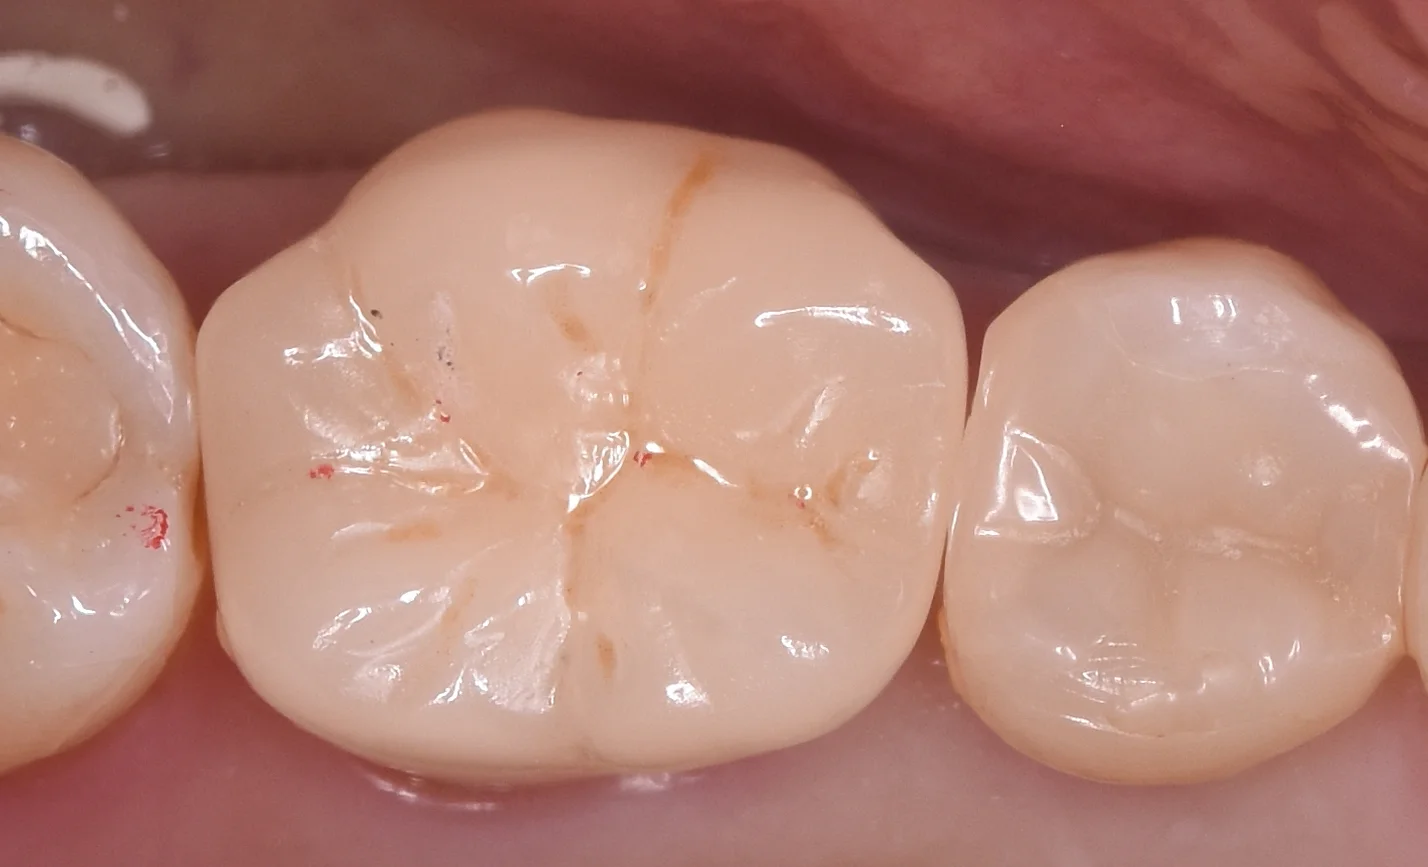

被せ物の調整を終え、Set直前の状態がこちらになります。

歯の亀裂で痛みが出たため、被せ物に。|坂寄歯科医院(取手市藤代) - 画像3

歯の色は前後の歯と調和しているのがわかるかと思います。